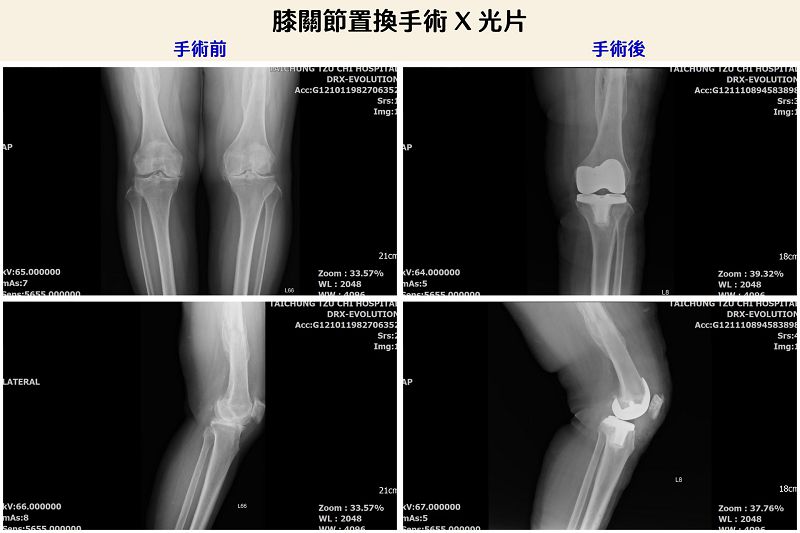

67歲陳女士膝關節疼痛多年,已經影響日常生活。台中慈濟醫院微創脊椎關節中心謝尚霖醫師診斷後,採用「ROSA Knee機器人手臂全人工膝關節置換手術」解除疼痛,術後膝關節疼痛與活動度顯著改善。

謝醫師指出,陳女士接受手術後,當日下午即下床使用拐杖助行器行走,出院一周回門診追蹤時,就能放開拐杖行走。膝關節疼痛與活動度顯著改善,口服止痛藥也減少很多,大幅提升生活品質。他解釋,ROSA Knee機器人手臂全人工膝關節置換手術,結合多項尖端科技,包括電腦智能運算、2D轉換3D立體解剖影像、即時定位追蹤導航、多動向機器人手臂等優勢,達到精準置換、減少軟組織傷害及術後疼痛與功能恢復,讓病人可以早期接受復健。